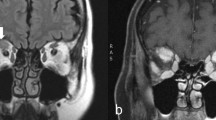

To explore the capability of 18F-FDG PET to differentiate the severity of GO patients, we compared PET parameter between the three EUGOGO severity grades (mild, moderate to severe, and sight threatening). MRI and PET images of patients with mild, severe, and unilateral GO are provided in Figs. 2, 3, and 4.

Transaxial MRI (panels A, D), PET (panels B, E), and fused slices of a 21-year-old patient with moderate, mainly left-sided GO reveal orbital tissue hypertrophy and 18F-FDG uptake, both more pronounced on the left side. The latter is more distinct on early static (panels A–C) vs. late static images (panels D–F)